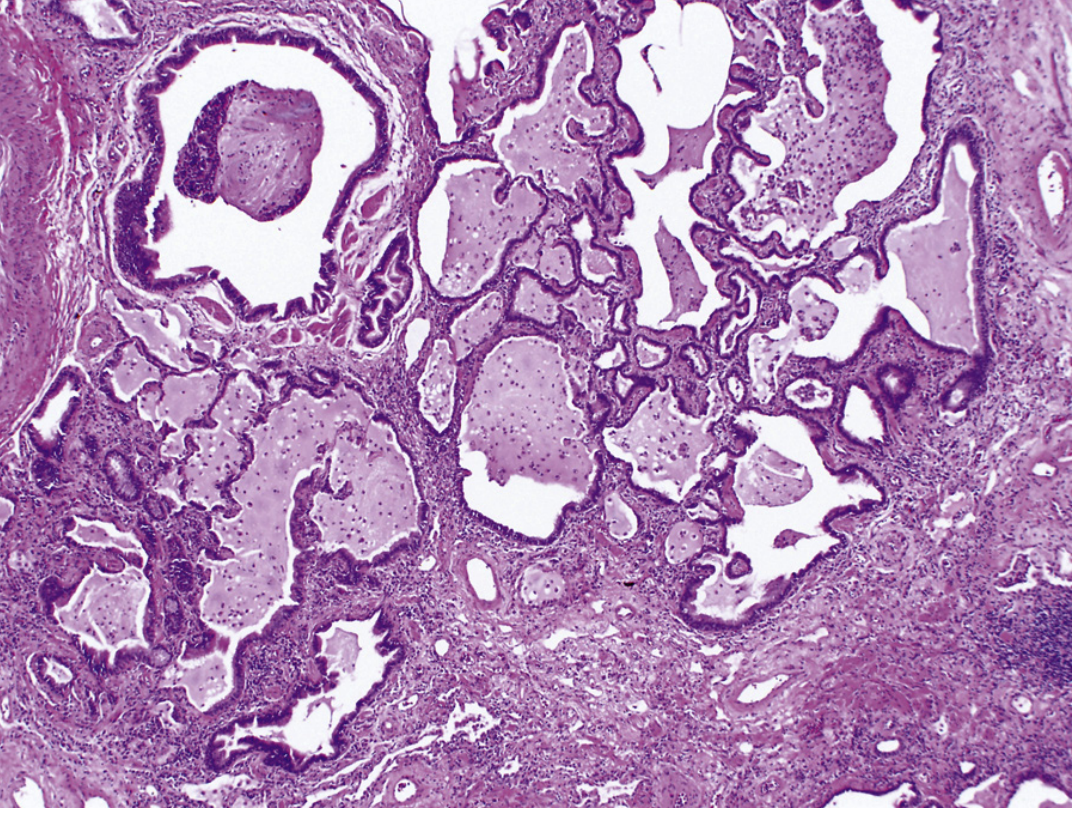

Histology of honeycomb lung in IPF — cystic spaces lined by metaplastic epithelium surrounded by dense fibrous bands

Fig. 89.5 — Honeycomb lung in IPF. Dense fibrous bands destroy alveolar architecture, forming cystic spaces lined by metaplastic epithelium. (×10, Murray & Nadel's Textbook of Respiratory Medicine)

Microscopic (UIP Pattern)

Hallmarks:

1. Spatial heterogeneity — normal lung alternating with architecturally effaced lung at low power

2. Temporal heterogeneity — early fibroblastic foci (loose myxoid stroma) alongside dense mature fibrosis

3. Honeycomb fibrosis — destruction of alveolar architecture forming cystic spaces lined by metaplastic/hyperplastic type II pneumocytes or bronchiolar epithelium

4. Mild lymphocytic inflammation; smooth muscle hyperplasia; pulmonary arterial hypertensive changes